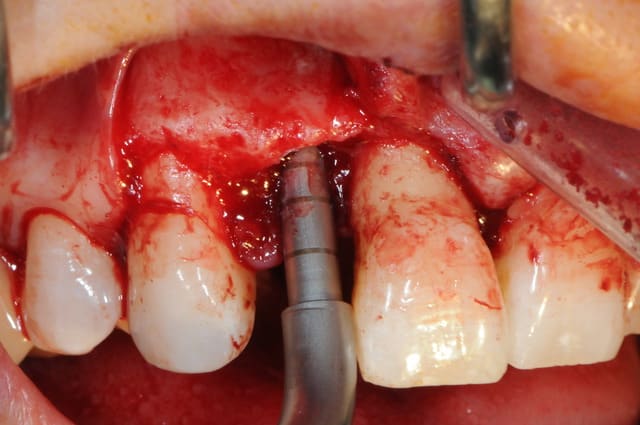

la chir...

extraction de 12 et 22 pour commencer et pour connaitre la limite maxi d'implantation dans la crête osseuse.

grosse déception quant à la table externe au niveau de 11

pour les axes, j'avoue que je me suis fait avoir comme une bleusaille (mais bon, j'en suis une), je me suis un peu laisser embarquer par l'axe des alvéoles. c'est dure l'implanto.